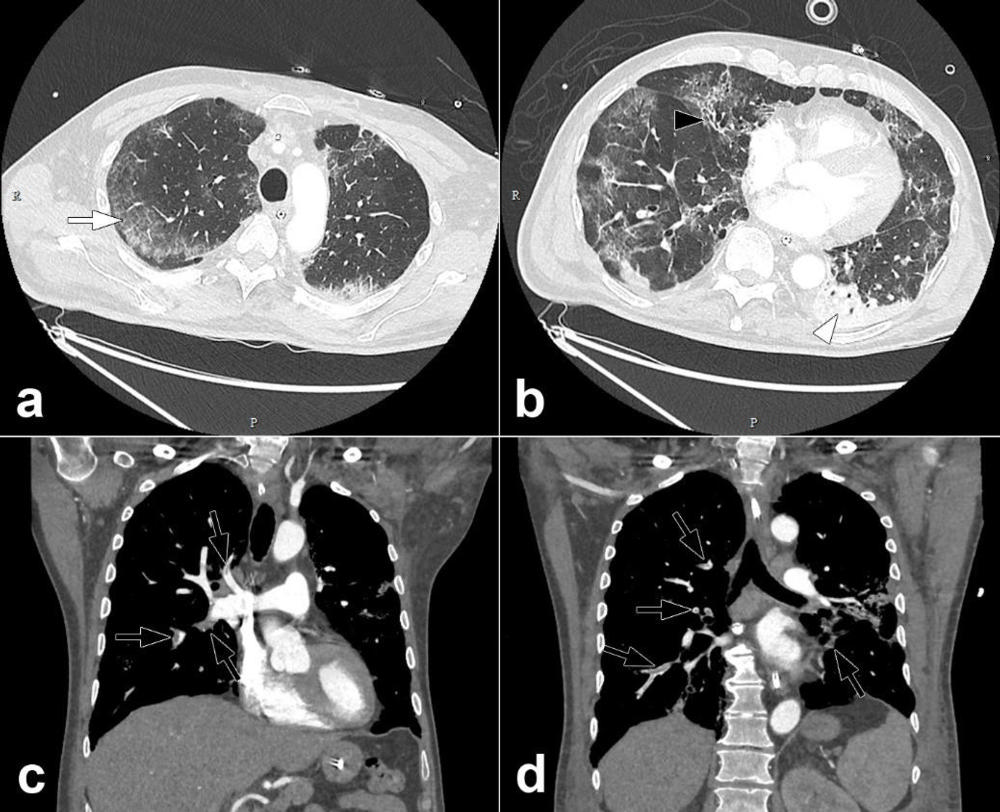

Figure 5. Pulmonary CT angiography of a 68-year-old male. The CT scan was obtained 10 days after the onset of COVID-19 symptoms and on the day the patient was transferred to the intensive care unit. Axial CT images (lung windows) (a, b) show peripheral ground-glass opacities (arrow) associated with areas of consolidation in dependent portions of the lung (arrowheads). Interlobular reticulations, bronchiectasis (black arrow) and lung architectural distortion are present. Involvement of the lung volume was estimated to be between 25% and 50%. Coronal CT reformations (mediastinum windows) (c, d) show bilateral lobar and segmental pulmonary embolism (black arrows). (Grillet, et al.)

High-res (TIF) version